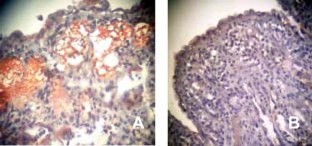

Fig 5.

Fig 6.